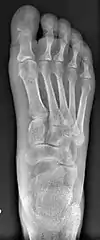

Bunion (hallux valgus) deformity is actually part of a complex of anatomical derangements of protruding mass (bunion), buckling of big toe (hallux valgus) and the bone behind it (metatarsus primus varus), displaced sesamoid bones (detrimental to the important walking function of big toe), collapsed metatarsal arch and several other secondary changes that are the domino effects of metatarsal primus varus. Thus, metatarsus primus varus correction has become the primary objective of all bunion surgeries.

Primus varus deformity

Primus varus deformity is the leaning of the first metatarsal bone away from the second metatarsal and towards the opposite foot (Fig. 1). As it leans over, its head sticks out to form the bunion bump and it also widens the forefoot to cause shoes feeling too tight. Thus when bunion pain becomes unmanageable, surgical correction is to narrow the forefoot by repositioning of the first metatarsal head back to its normal position. This can be done by osteotomy (bone-breaking), soft tissue (non-osteotomy) or fusion techniques.